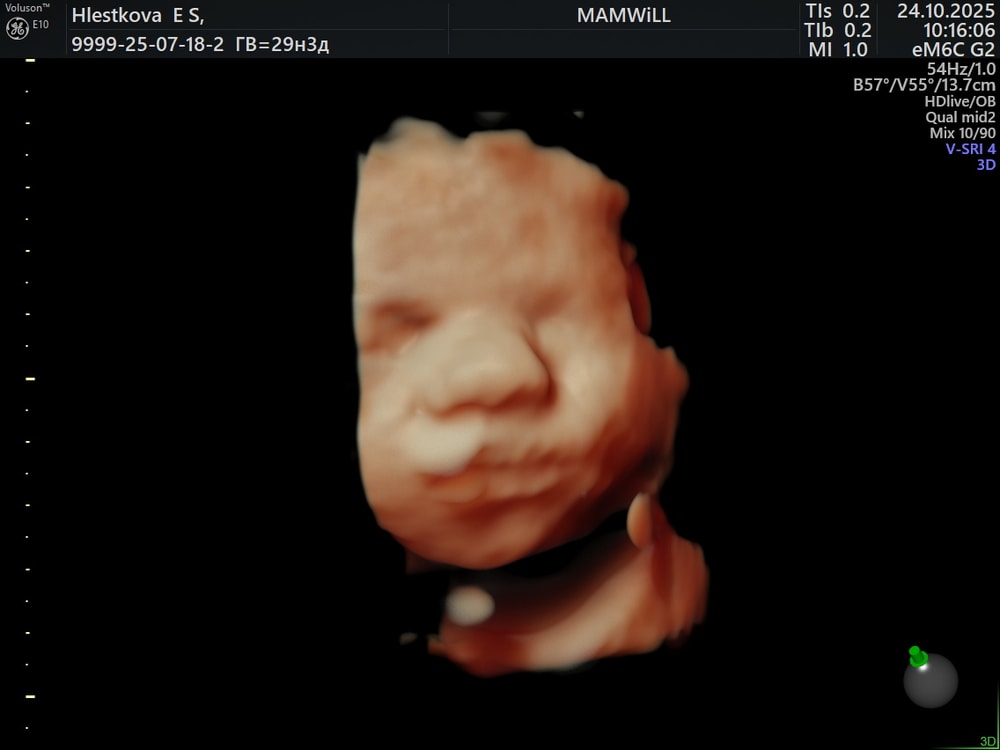

29 недель и 3 дня

Сегодня были на долгожданном 3D узи

Все соответствует сроку😍

Сыночка такой лапусик, похож очень на меня, но эмоции и гримасы мужа 😏

Пришлось поуговаривать, чтобы сделать красивые кадры 🤣

Весь в мужа- фоткаться не хочет и прячется 🤣

Весит 1400 грамм, лежит в головном предлежании - все как нужно!